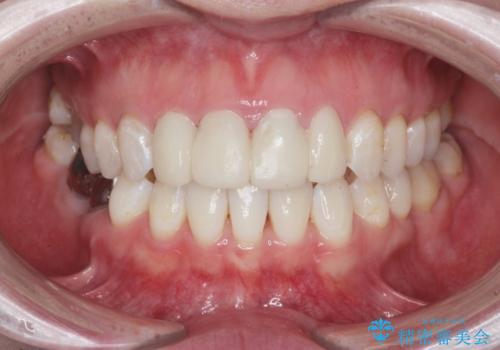

- 仮歯のまま放置してしまい、変色を改善しきれいなセラミッククラウンをいれたい、と希望され来院されました。

特に虫歯の再発や神経の症状等問題を認めなかったので、審美的に優れるセラミッククラウンに仮歯を置き換えていきます。

セラミッククラウンは長期的に変色しづらく、汚れのつきにくい審美製を長期的に保つことのできる治療方法です。